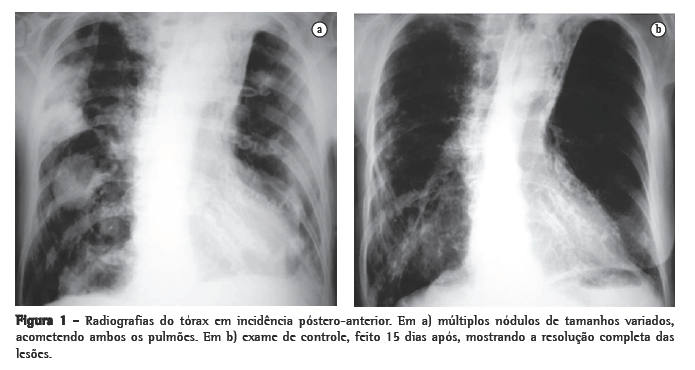

Foi realizada tomografia computadorizada (TC) do tórax, que confirmou a presença dos nódulos com tamanhos variados, sendo alguns escavados (Figura 2). Três amostras seguidas de escarro com pesquisa de bacilos álcool-ácido resistentes e fungos (coloração pela prata) foram negativas. A bacterioscopia (Gram) mostrou a presença de bactérias filamentosas nas três amostras colhidas de escarro, fortemente sugestivas de Nocardia spp., confirmada pela coloração de Ziehl- Neelsen, mostrando a característica resistência parcial à solução álcool-ácido (Figura 3).

A apresentação radiológica torácica é inespecífica. Os achados radiológicos mais comuns são as consolidações e os grandes nódulos irregulares.

Nódulos, massas escavadas, derrame pleural, pneumotórax, opacidades em vidro fosco e padrões intersticiais podem também ocorrer.(1,4,5,11) Alguns estudos mostram que, em pacientes HIV positivos, existe um percentual maior de lesões escavadas.(8) A consolidação alveolar nos lobos superiores é muitas vezes confundida com tuberculose pulmonar.(6) Embora as alterações vistas na TC sejam ­semelhantes às das radiografias convencionais, a TC é superior na demonstração da exata localização e extensão das lesões, assim como na diferenciação entre lesões pulmonares e pleurais.(5) No caso relatado, a paciente apresentava imagens nodulares de tamanhos variados, disseminadas por ambos os pulmões, e algumas delas escavadas.